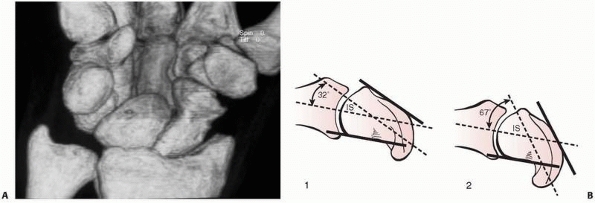

![]() |

|

FIGURE 29-14 A. CT scan of a scaphoid fracture that has healed with a humpback deformity. B.

Schematic drawing of scaphoid: (1) normal scaphoid, (2) humpback deformity. The normal intrascaphoid angle (IS) is 30 degrees ± 5 degrees. The humpback deformity angle measure 67 degrees and the normal scaphoid 32 degrees. |